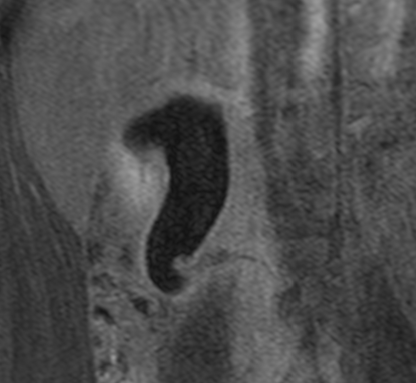

In diesem Fallbericht beschreiben wir einen 17-jährigen Patienten, der mit rez. ausgeprägten Koliken in unserer Abteilung vorstellig wurde. Initial erfolgte bei Hydronephrose °III und pos. Steinanamnese des Vaters eine CT-Abdomen nativ, welche bereits den V.a. einen retrocavalen Harnleiter rechts ergab. Eine Szintigraphie bestätigte eine urodynamisch relevante Obstruktion bei ausgeglichener Nierenfunktions. Bei Symptomatik erfolgte eine retrograde Ureteropyelographie mit JJ-Einlage. Im weiteren Verlauf wurde noch eine MRT-Angiographie durchgeführt, welche den Befund eindeutig bestätigte. Daraufhin erfolgte am 10.11.2025 die daVinci-assistierte Ureterureterostomie rechts in Linksseitenlage. Hierfür wurden 4 Arbeitstrokare und ein Kameratrokar verwendet. Die Gesamtoperationszeit lag bei 181 min, die reine Konsolenzeit bei ca. 100 min. Intraoperativ erfolgte ein JJ-Wechsel. Die Anastomose erfolgte mit einer 4.0 Quill-Naht in fortlaufender Technik. Der Blutverlust lag bei ca. 20 ml. Postoperativ waren die Schmerzen mit Novalgin gut beherrschbar. Die Entlassung erfolgte am 5. postoperativen Tag nach DK-Entfernung.